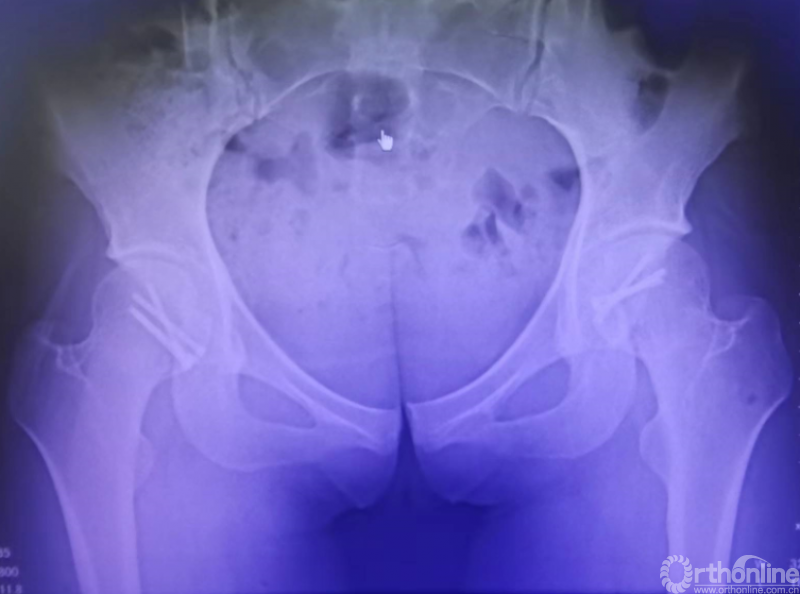

术后影像学资料

术后1年